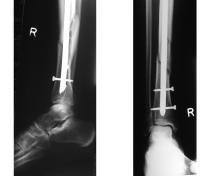

内固定:以手术的方式将金属骨钉钉合在骨折部。

外固定:从体外固定骨折部